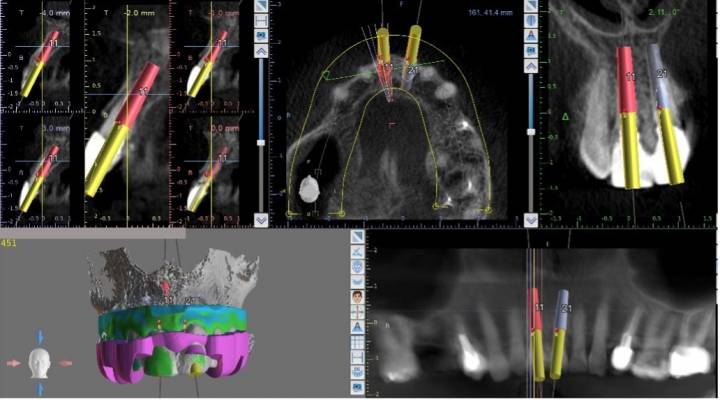

Our cutting-edge technology ensures precise implant placement, shorter procedure times, reduced post-procedure discomfort, and exceptional aesthetic results. For instance, let’s take a closer look at some of the technological components that enable Alpha Dental Excellence to offer unparalleled tooth replacement options, whether for a single tooth, multiple teeth, or a full set.

GuidedSMILE Dental Implant Planning

The proprietary GuidedSMILE system enables us to plan the entire implant procedure in advance, before even using the first instrument. By utilizing the detailed data from the 3D cone beam scan, we can map out the surgery with precision, eliminating guesswork and significantly improving the predictability and safety of the procedure.

GuidedSMILE Surgical Implant Guides

During the dental implant records appointment, the information gathered is transformed into a physical surgical guide. This guide, resembling a chrome overlay similar to a plastic mouthguard, contains precise holes that indicate the exact locations for implant placement. These holes control the depth and angle of the drill used during the procedure, ensuring the accurate placement of each implant for every patient.